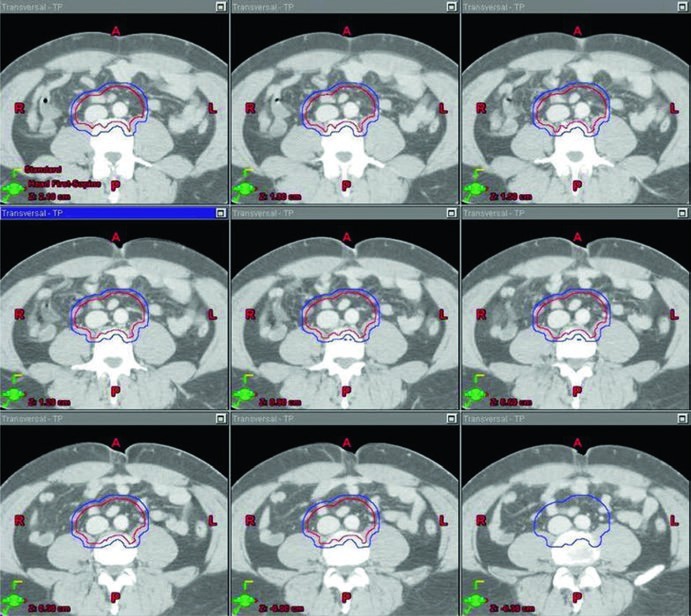

No estágio II, a resposta do capítulo muda de escala. Aqui, os pacientes com seminoma puro podem ser tratados com um campo dogleg, com dose total de 30 Gy para estágio IIA e 36 Gy para estágio IIB. Como alternativa, o texto cita quimioterapia primária, tipicamente com etoposídeo e cisplatina, com ou sem bleomicina, por 3 a 4 ciclos. Mais uma vez, o livro organiza radioterapia como uma opção sólida, mas não como único caminho possível.

O ponto técnico mais útil é que o dogleg não nasce do zero. Ele começa com o mesmo contorno de cava inferior e aorta usado no estágio I e, em seguida, incorpora vasos ilíacos comuns, porções proximais dos ilíacos internos até a emergência da glútea superior e vasos ilíacos externos até a borda superior do acetábulo, com expansão de 1,2 cm respeitando limites anatômicos. Depois disso, o capítulo pede contorno da doença nodal grosseira, o GTV, com expansão de 0,8 cm respeitando a anatomia, formando um CTV nodal. A união do CTV vascular com o CTV nodal produz o CTV inicial.

Esse campo inicial recebe expansão de 0,5 cm mais 0,7 cm até a borda do bloco para compor o PTV inicial, ainda na faixa de 20 a 25,5 Gy com frações de 1,5 a 2,0 Gy. O boost em conedown segue a mesma lógica geométrica aplicada ao CTV nodal, também com 0,5 cm mais 0,7 cm até a borda do bloco, até completar 30 a 36 Gy em 2 Gy por fração. O capítulo ainda acrescenta uma regra simples e prática para a doença visível: garantir margem de 2 cm ao redor de toda adenopatia grosseira visível.

Os marcos anatômicos ajudam a não perder o eixo do campo. Superiormente, o limite permanece no topo de T11, com a mesma nota de que algumas fontes usam topo de T12. Inferiormente, o capítulo posiciona o limite no topo do acetábulo, embora algumas fontes recomendem o meio ou a base do forame obturatório. A borda lateral acompanha as pontas dos processos transversos das vértebras lombares, tipicamente em torno de L3, considerando a posição dos rins, e se estende inferiormente para cobrir a borda lateral do acetábulo. Para seminoma à esquerda, a cobertura do hilo renal esquerdo volta a aparecer como opcional.

A figura de boost fecha esse raciocínio muito bem. Ela mostra, em um exemplo de estágio IIA, a diferença entre GTV em amarelo, CTV em vermelho e PTV em azul. Não é só uma ilustração bonita; é a prova visual de que o capítulo separa volume eletivo, volume inicial e volume de reforço com precisão suficiente para orientar planejamento real.

Tabela 27.2. Volumes sugeridos para seminoma testicular estágio II

No estágio II, a tabela do capítulo descreve a montagem do dogleg passo a passo. Ela vale a leitura com calma porque concentra, em poucas linhas, vasos, doença macroscópica, blocagem e dose.

| Volume-alvo e dose | Definição baseada em TC e anatomia vascular | Definição baseada em marcos anatômicos |

|---|---|---|

| CTV inicial | Usar os mesmos contornos e expansões de cava inferior e aorta descritos na Table 27.1. Depois, contornar vasos ilíacos comuns, porções proximais dos ilíacos internos até a origem da glútea superior e vasos ilíacos externos até a borda superior do acetábulo, com expansão de 1,2 cm respeitando limites anatômicos. Contornar a doença nodal grosseira (GTV) e expandir 0,8 cm respeitando limites anatômicos. Combinar CTV vascular e CTV nodal para formar o CTV inicial. |

Borda superior: topo de T11 (algumas fontes recomendam topo de T12) [6]. Borda inferior: topo do acetábulo (algumas fontes recomendam meio ou base do forame obturatório) [6]. Borda lateral: pontas dos processos transversos lombares, tipicamente em L3 com consideração da localização renal, estendendo-se para cobrir a borda lateral do acetábulo na porção inferior do campo. |

| PTV inicial 20–25,5 Gy em 1,5–2,0 Gy por fração |

Expandir o CTV inicial em 0,5 cm + 0,7 cm até a borda do bloco. | Para seminoma à esquerda, os estudos de mapeamento nodal sugerem que cobrir o hilo renal esquerdo é opcional [7]. |

| PTV de boost em conedown Total de 30–36 Gy em 2 Gy por fração |

Expandir o CTV nodal em 0,5 cm + 0,7 cm até a borda do bloco. | Garantir margem de 2 cm ao redor de toda adenopatia grosseira visível. |

Fonte: Target Volume Delineation and Field Setup, 2nd Edition (Table 27.2).

É aqui que o capítulo ganha força prática. Em vez de opor “campo clássico” e “planejamento moderno”, ele mostra um método detalhado para construir o dogleg em cima de vasos, marcos ósseos e doença visível. Para estágio IIA, a dose total de 30 Gy acompanha esse desenho. Para estágio IIB, o mesmo raciocínio segue até 36 Gy. O resultado é uma receita menos automática do que muitos resumos rápidos sugerem.